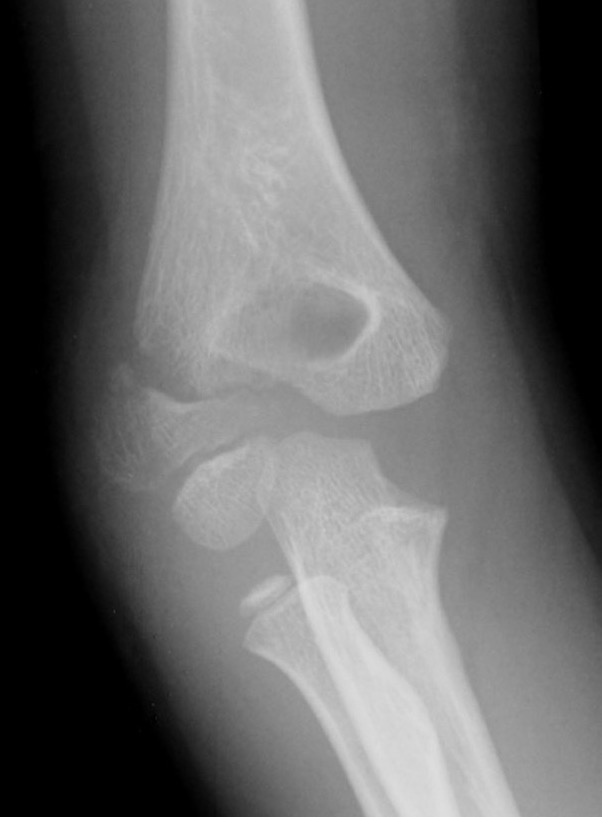

X-ray

Undisplaced

- typically metaphyseal flake

- looks minimally displaced on AP and lateral

- perform an internal oblique x-ray to exclude displacement

Injured left elbow v injury right elbow